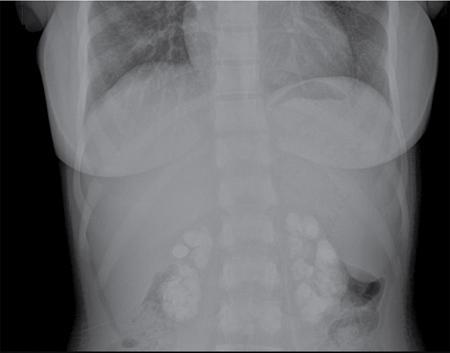

The term nephrocalcinosis was coined in 1934 by Fuller Albright. Nephrocalcinosis refers to the deposition of calcium salts (oxalate and phosphate) in the renal parenchyma. It can be medullary, cortical or combined. Medullary nephrocalcinosis is the most common type and is seen in 98% of cases. Nephrocalcinosis can be incidentally detected on imaging in patients with normal kidney function or in patients with acute or chronic kidney injury. Multiple conditions can cause nephrocalcinosis, and prognosis depends on the underlying aetiology. Nephrocalcinosis is in most cases, an asymptomatic, chronic and slowly progressive disease that is discovered as an incidental finding during radiographic imaging. Such imaging may be obtained as part of evaluation of nephrolithiasis, which often coexists with nephrocalcinosis. However, some patients present with clinical symptoms that are related to nephrocalcinosis or to the causative process. These include renal colic, nocturia, polyuria and polydipsia. Some causes of nephrocalcinosis can present acutely with renal failure. Nephrocalcinosis can occur secondary to varying aetiologies. Based on the location of calcium deposition, nephrocalcinosis is classified as medullary, cortical or global (Box 10.12.4.1.1). Medullary nephrocalcinosis is further classified based on the underlying metabolic derangement. CAUSES OF NEPHROCALCINOSIS Conditions causing hypercalcaemia and hypercalciuria Conditions causing hypercalciuria In hypercalcaemia, metastatic calcification takes place in normal renal tissue, leading to medullary nephrocalcinosis. Hypercalcaemia results in hypercalciuria, leading to higher incidence of urolithiasis. Severe prolonged hypercalcaemia leads to irreversible renal impairment due to tubulointerstitial damage which can present as small smooth kidneys. On imaging, chronic hypercalcaemia is usually seen as diffuse, symmetric medullary nephrocalcinosis with small, smooth kidneys. Medullary nephrocalcinosis is seen only in with type I or distal renal tubular acidosis. There is progressive renal insufficiency in these patients. Urolithiasis is common due to hypercalciuria and hypocitraturia. Medullary calcifications are diffuse and symmetric, involving all renal pyramids of both kidneys. Kidneys are normal in size and maintain normal contour. Medullary sponge kidney is thought to be a congenital disorder in which there is ectasia of the renal tubules. It is often an incidental finding of little clinical significance. However, there is increased risk of urolithiasis and pyelonephritis. Ectasia causes urine stasis and precipitation of calcium and related minerals. Calcifications are usually rounded and multiple, arranged radially, emerging from the renal papilla. Calculi in dilated renal tubule appears to increase in size on postcontrast images, seen as growing calculus sign. Most patients with medullary sponge kidney have normal-sized kidneys. Analgesic nephropathy, secondary to prolonged intake of large doses of NSAIDs can cause medullary nephrocalcinosis and chronic renal insufficiency. Medullary nephrocalcinosis detected in combination with bilateral small, scarred kidneys strongly suggests analgesic nephropathy. In hyperoxaluria there is abnormality in the enterohepatic metabolic pathways. This leads to increased excretion of oxalates in urine, causing medullary nephrocalcinosis and formation of calcium oxalate stones. Hyperoxaluria can also cause cortical nephrocalcinosis. Primary hyperoxalosis is an irreversible condition and causes death at a young age. Secondary hyperoxaluria is caused by small bowel resection and extensive disease of the small bowel. Renal tuberculosis can cause calcifications of the urinary tract in 10% of cases. Renal TB is usually seen in one kidney and starts at a single renal papilla. As the infection progresses, it extends into the renal calyx and is associated with papillary necrosis. Infection can then extend along collecting system leading to inflammation and fibrosis. In later stages it presents as hydronephrosis, eventually leading to autonephrectomy. Asymmetric unilateral renal scarring or stricturing with associated nephrocalcinosis is highly indicative of renal tuberculosis. Cortical nephrocalcinosis is due to dystrophic calcification following renal parenchymal tissue destruction. Major cause of cortical nephrocalcinosis is chronic glomerulonephritis. It is associated with chronic renal failure. On imaging it can present as small smooth kidneys with shell-like calcifications involving the renal cortex. Acute cortical necrosis is another major cause of cortical nephrocalcinosis. It is caused by severe hypotension, secondary to complications of childbirth, sepsis or severe blood loss. It can also be secondary to ingestion of nephrotoxins, such as ethylene glycol. Medullary nephrocalcinosis can present as fine, stippled, coarse or confluent calcifications in the renal pyramids (Figs 10.12.4.1.1–10.12.4.1.2 and 10.12.4.1.5A). Cortical nephrocalcinosis presents as punctate or ‘tram line’ cortical calcifications. Nephrocalcinosis is not seen on plain radiographs if attenuation is less than 100 Hounsfield units (HU) or if the size is less than 2 mm.